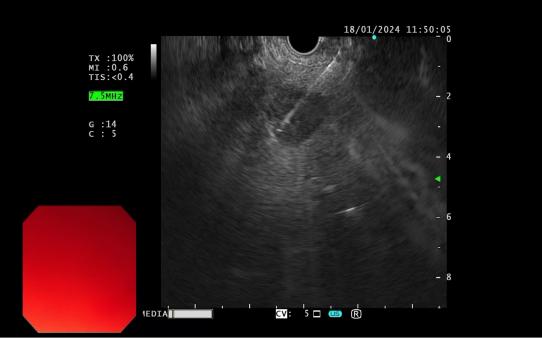

4d818f53b089499c860884ad0d9dab6c.Jpega62e29074df94ee9a5dace0b932c125d.Jpeg

發現內源性低回聲病灶        實時超聲引導下對病灶的細針穿刺活檢

內鏡超聲引導下細針穿刺抽吸術(EUS-FNA):治療對于性質不明的胰腺實性占位性病變;對于經CTMRI或 EUS 等檢查不能確定性質的胰腺囊性病變;對于消化道毗鄰組織中性質不明的占位性病變或淋巴結腫大(如縱隔、上腹部等部位病變);長徑>2cm需要手術切除但具有高手術切除風險,或不能切除的消化道上皮下腫瘤的鑒別診斷。